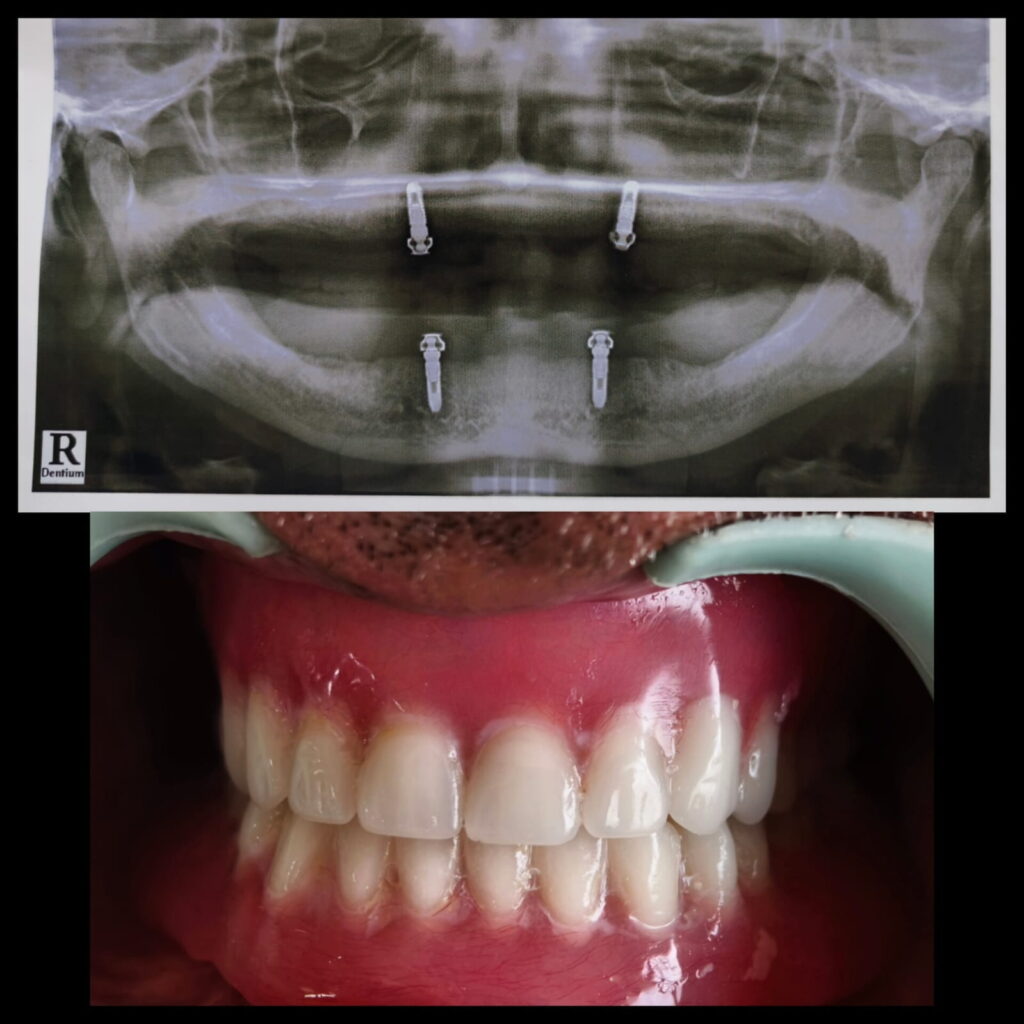

Implant supported overdenture case